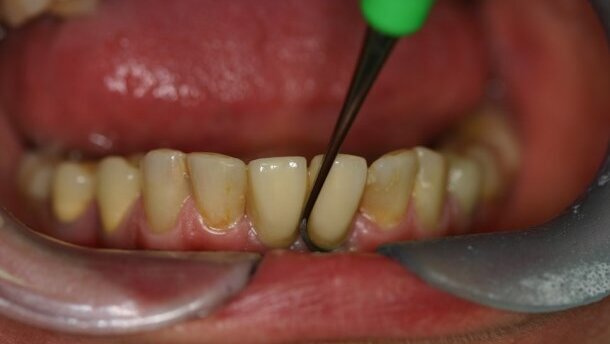

Objawy periimplant mucositis to oznaki zapalenia tkanek miękkich wokół implantu (takie jak: zaczerwienienie, obrzęk, stan ropny) oraz krwawienie przy delikatnym sondowaniu (0,25 N).3,13,7

Leczenie periimplant mucositis opiera się na postępowaniu niechirurgicznym. Polega na usunięciu nad- i poddziąsłowego biofilmu poprzez zastosowanie miejscowo środków przeciwbakteryjnych z równoczesnym oczyszczeniem złogów i tkanki zapalnej, ultradźwiękami i kiretami przeznaczonymi do oczyszczania implantów oraz poprzez zastosowanie laserowej terapii w postaci fotoaktywnej dezynfekcji.5,25,26

Rozpoznanie kliniczne periimplantitis opiera się na stwierdzeniu obecności zapalenia tkanek miękkich z krwawieniem podczas sondowania, przy równoczesnej utracie kości wokół implantu (sondowanie kieszeni to głębokość PPD ≥5 mm, PPD – Pocket Probing Depths) z lub bez wysięku ropnego podczas badania, na rentgenogramie widoczna utrata kości ≥2 mm, w charakterystycznym kształcie „spodka lub krateru”.27,7 Ważna jest również diagnostyka różnicowa, w tym określenie i ewentualne wyeliminowanie przeciążenia w zgryzie.6,25